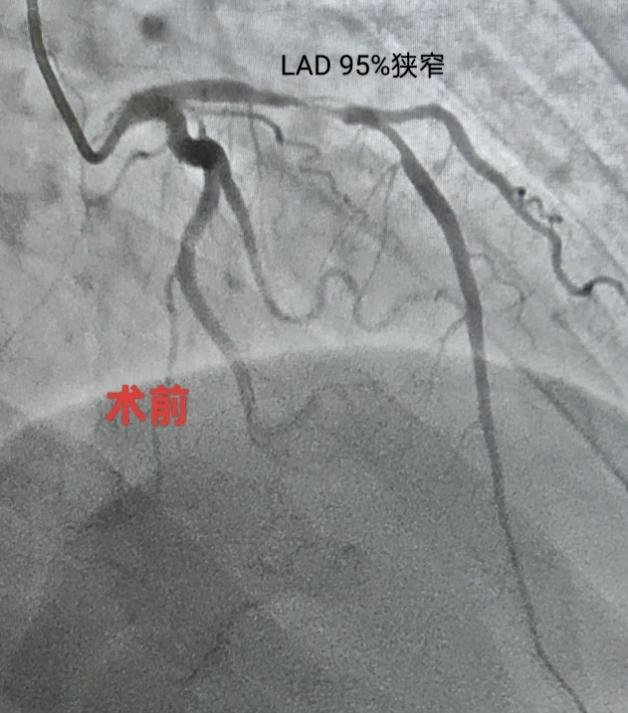

(术前术后冠状动脉对照)

听说要做心脏手术,王女生十分紧张,“总感觉自己得了大病”。魏望江便亲自前去劝解。为了让患者安心,同时确保第一例心脏介入手术顺利开展,魏望江特意邀请北京地坛医院心内科副主任(主持工作)管浩等人讨论病情,在管浩主任的指导下,根据患者情况制定合理的手术和治疗方案。4月16日,由北京地坛医院董茜、郑迪两位专家主刀,徐州医院导管室医护人员参与,为王女士行心脏冠状动脉造影及支架置入术。术后患者恢复良好,无并发症,各项检查指标均在合理范围,即将办理出院。